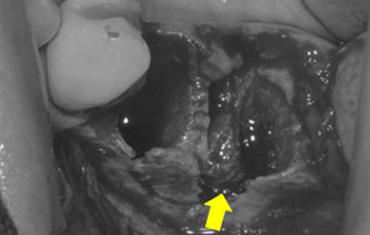

타 치과의 뼈 이식 후 골조직